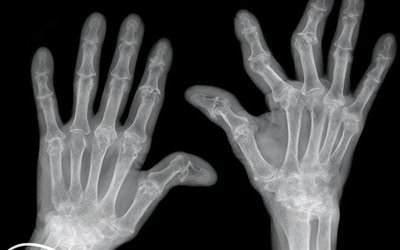

Rheumatoid Arthritis: Immune complexes (IgM and IgG) deposit in joints, causing chronic inflammation and joint damage.